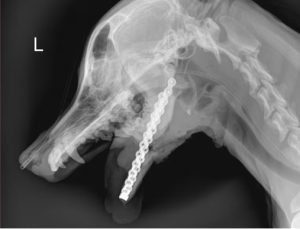

La explosión provocó graves lesiones. Canela perdió la mandíbula inferior y sufrió múltiples fracturas. El informe del Ferrer Centro Veterinario detalla una fractura conminuta de la sínfisis mandibular y fracturas transversales en las ramas de la mandíbula. También se registró fractura del colmillo superior izquierdo y osteomielitis.

Debido a la gravedad del daño, los especialistas realizaron una mandibulectomía. Posteriormente, el equipo veterinario logró colocar la prótesis mandibular que permitió devolverle funcionalidad a la zona afectada.